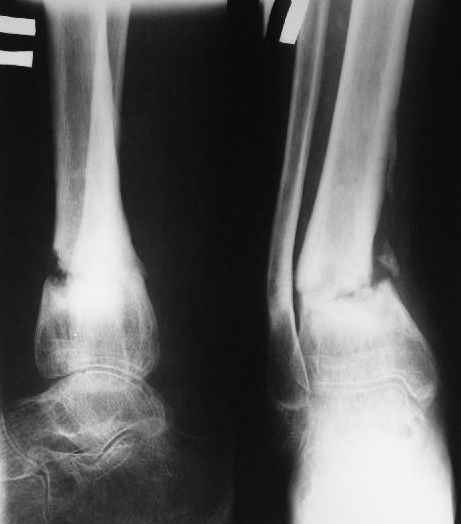

В январе 2005: варусная деформация н\3 голени, болевой с-м, комбинированная контрактура г\стопного сустава, нейропатия м\берцового нерва сохраняется слабость разгибания 1 пальца.

Операции: 1 Клиновидная резекция на вершине деформации м\берцовой кости.

2 Тугоподвижный ложный сустав н\3 б\берцовой кости. Рубцы выполняющие пространство между отломками, канал проксимального отломка иссечены.